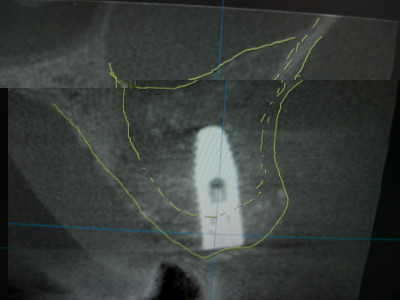

今日のオペは入れ歯固定用のインプラントの埋入オペでした。

ただこの部位は上顎洞底から歯槽頂までの厚みがありませんでしたので、サイナスリフトして骨造成を行い、同時法にてインプラント埋入致しました。